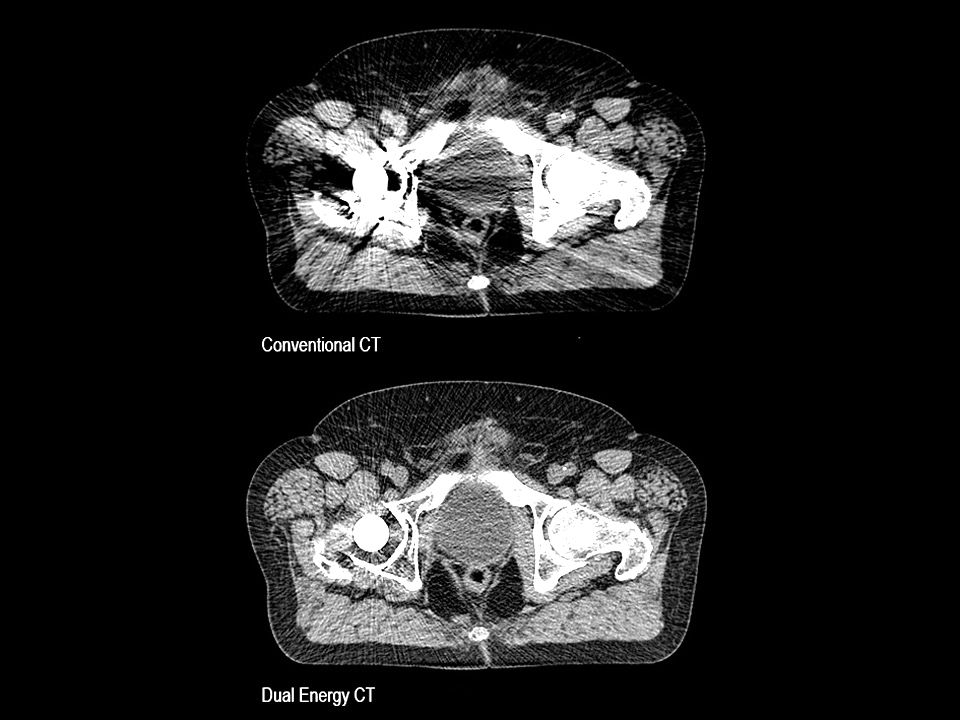

Monoenergetic imaging

Customize your image impression – reducing metal artifacts.